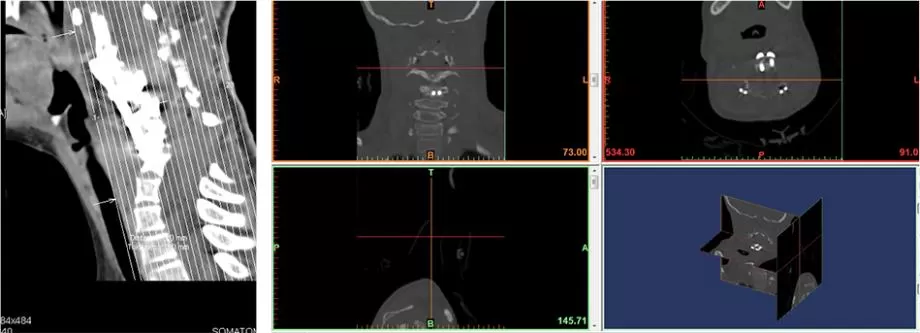

Because this is a medical project, we imported the CT scan and MRI data into professional 3D medical printing software to screen and convert the images into solid models.

With the help of software, we separated the patient's spine and trachea. The spine part that needs to be directly 3D printed is marked in orange, while the trachea part that needs to be made separately is marked in gray.

In the software we can clearly see the location and extent of the patient's esophageal lesions.